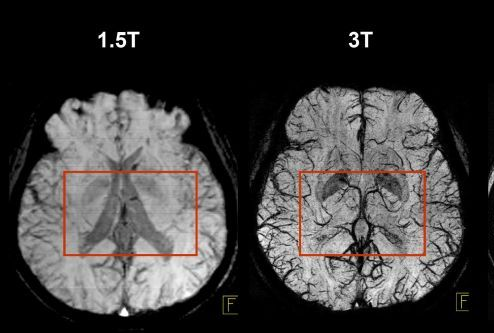

1.5 Tesla Imaging Method

1.5 T imaging uses a magnetic field strength of 1.5 Tesla. It is used for routine, whole-body imaging and is found in public hospitals:

Pros

is more tolerable for sick patients

less movement artefacts

safer

3 Tesla Imaging Method

3 T Imaging uses a magnetic field strength of 3 Tesla and is high resolution imaging.

Pros

has more signal

decreased scan time

Cons

More chance of burns and projectiles

Harder for patients to thermoregulate so increased movement